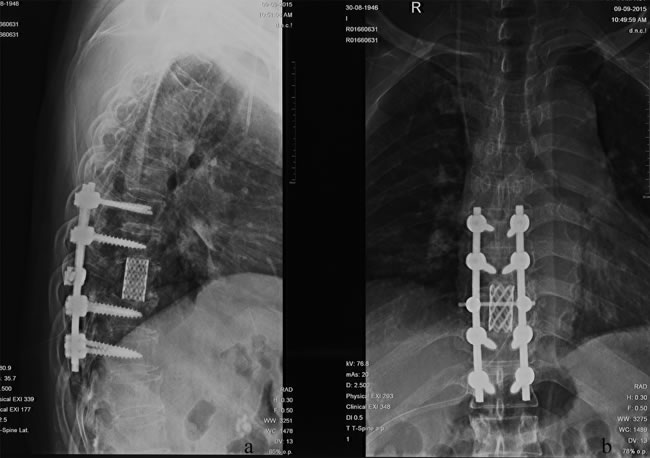

HCC is the second leading cause of cancer-related death in China and the third worldwide [24, 25]. Because of improved diagnosis and therapeutic modalities for primary HCC, more cases of extrahepatic metastases, especially bone metastasis, have been detected in recent years. MSCC from primary HCC can be seen as a certain probability in clinical practice and remains a challenge for clinicians. In patients with the terminal stage of advanced cancer associated with persistent pain and neurological defects, surgical intervention could be an effective way to relieve symptoms directly and enhance the quality of life. Figure 3 and 4 illustrate the preoperative radiologic findings and postoperative condition (54 months after spine surgery) of a representative patient who ever underwent excision of primary HCC and metastatic lesion. And he experienced PFS during a final follow-up of 59.0 months, with a satisfactory quality of life after surgery and adjuvant therapies.

Figure 4: A.-B. Postoperative X-ray outcome at the final follow-up 59.0 months after surgeries and adjuvant therapies.